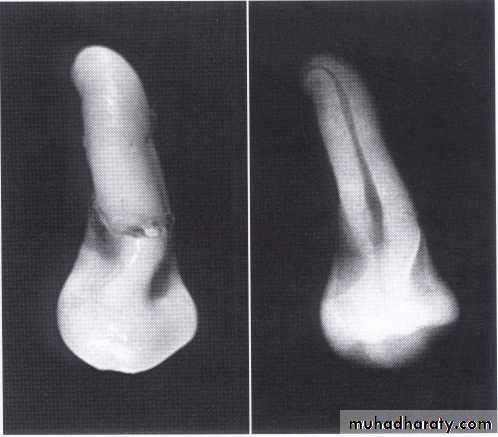

• Fusion of the left mandibular central and lateral incisors (twoindividual roots, two root canals and two joined crowns).

Gemination of right mandibular central incisor has one root, one root canal and a partially bifid dental crown.